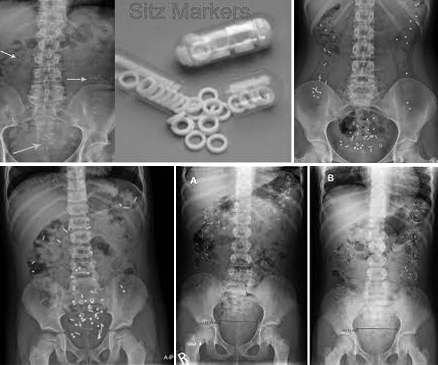

ให้รักษาที่สาเหตุ ถ้าคนไข้มีอาการท้องผูกมานาน โอกาสที่จะเป็นโรคร้ายแรง เช่น โรคมะเร็ง จะมีน้อย ส่วนมากในกลุ่มคนไข้ที่เป็นมานานมักจะเป็นท้องผูกเรื้อรัง แพทย์จะทำการซักประวัติและตรวจร่างกาย ในรายที่สงสัยว่าจะมีความผิดปกติ หรือมีอาการเตือนถึงโรคร้ายแรง เช่น ปวดท้องมาก ถ่ายเป็นมูกเลือด น้ำหนักลด อาจจะมีการตรวจเลือด หรือแนะนำให้มีการตรวจเพิ่มเติมพิเศษ เช่น การส่องกล้องลำไส้ใหญ่ sitz mark, manometry เพื่อดูการทำงานของตัวลำไส้